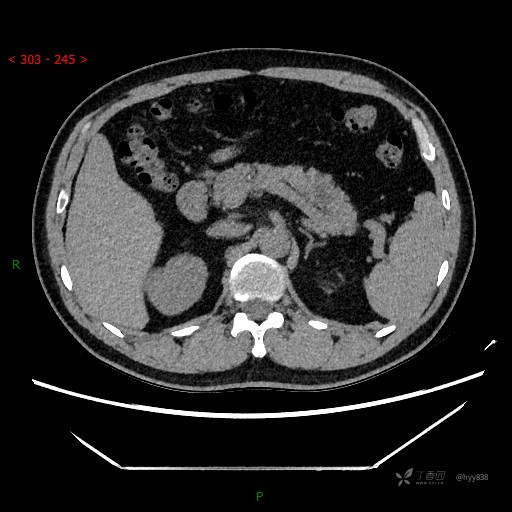

静脉期